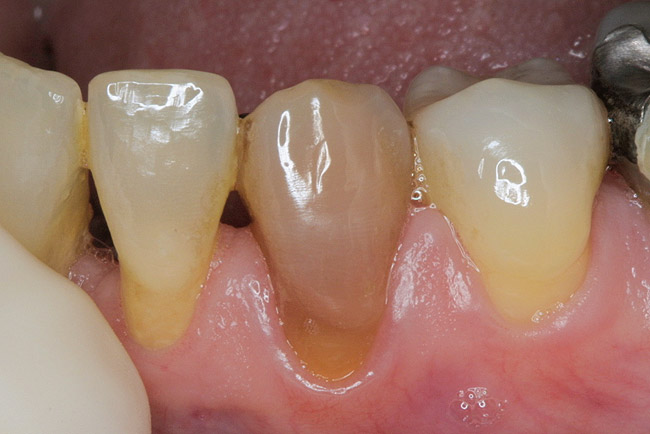

Figure 4  Endodontic therapy was attempted on a tooth with calcific metamorphosis, with subsequent perforation and file fracture in the PDL.

Figure 4

Pulp necrosis as evidenced by periapical radiolucency is an infrequent sequela to PCO occurring in approxi­mately 7% to 16% of cases; consequently, prophylactic endodontic therapy is not recommended by most authors.28,39-41 Teeth with PCO likely have diminished healing capacity, and it is not well established whether a secondary trauma or additional dental treatment causes necrosis. In some instances, such as preparing a tooth with PCO for an abutment, it may be prudent to perform prophylactic endodontic therapy before the definitive restorative procedure. A recent article by daCunha and colleagues suggests implementing endodontic therapy prior to development of a periapical radiolucency in a tooth with PCO, based on two major considerations: (1) the technical difficulty and complications that may occur in treating these teeth; and (2) their review of a study that demonstrated a 97.9% success rate for teeth treated without periapical radiolucencies vs a 62.5% success rate for teeth treated with periapical radiolucencies.42 Specific clinical situations will dictate clinical decisions; however, given the relatively low incidence of pulp necrosis in teeth with PCO, endodontic treatment usually is not recommended in the absence of a periapical radiolucency or symptoms. Nonetheless, if a periapical lesion develops, endodontic therapy can be both challenging and fraught with complications (Figure 4). The use of operatory microscopes in the hands of a skilled clinician is warranted and improves the chances of a successful outcome.